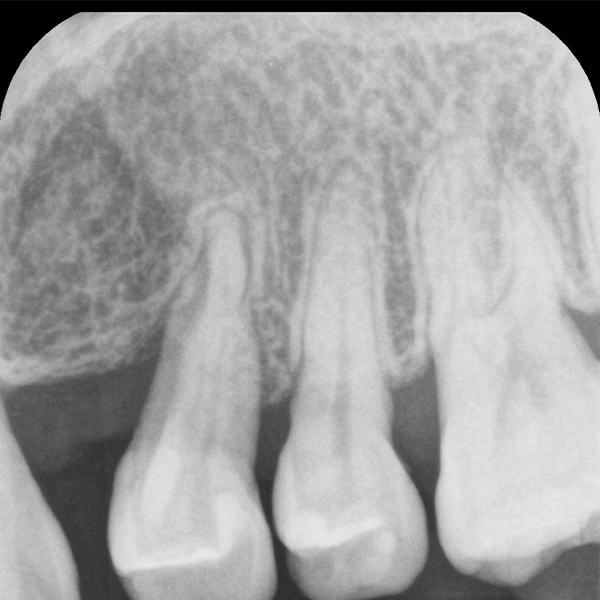

歯周組織再生療法の症例

Before

千葉市若葉区の歯周組織再生療法

57歳 女性

歯周組織再生療法

治療の期間・回数:10日間、2回(手術と抜糸)

※この患者さまは矯正治療も平行して行っているため、トータル2年間、25回

治療の価格:約10,000円(税込11,000円 )※健保で対応

治療のリスクや副作用:ご自身でのプラークコントロール、及びメンテナンスをしないと治療は成功しません。外科処置なので他の歯科での外科処置、例えば抜歯のときと同じリスクがあります。(腫れたり、痛んだりなど)喫煙者は適応不可です。(成功率が低いため)

場合によって2週間くらい顔面皮膚にアザができます。これは、時間の経過とともに消えますのでご安心ください。定期管理しなかったり、元々の歯肉の厚みが薄いと歯肉退縮が起こることがあります。